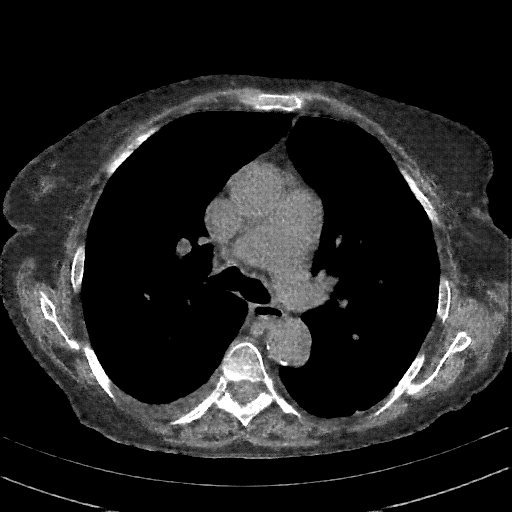

Reconstructed NATIVE CT scan (cycle consistency)

Full window (WL 1023.5, WW 4095 β†’ Low βˆ’1024, High +3071)

Actual HU range: [-1024.0, 1239.7]

Lung window (WL -600, WW 1500 β†’ Low βˆ’1350, High +150)

Actual HU range: [-1125.1, 150.0]

Mediastinum window (WL 40, WW 400 β†’ Low βˆ’160, High +240)

Actual HU range: [-160.0, 240.0]